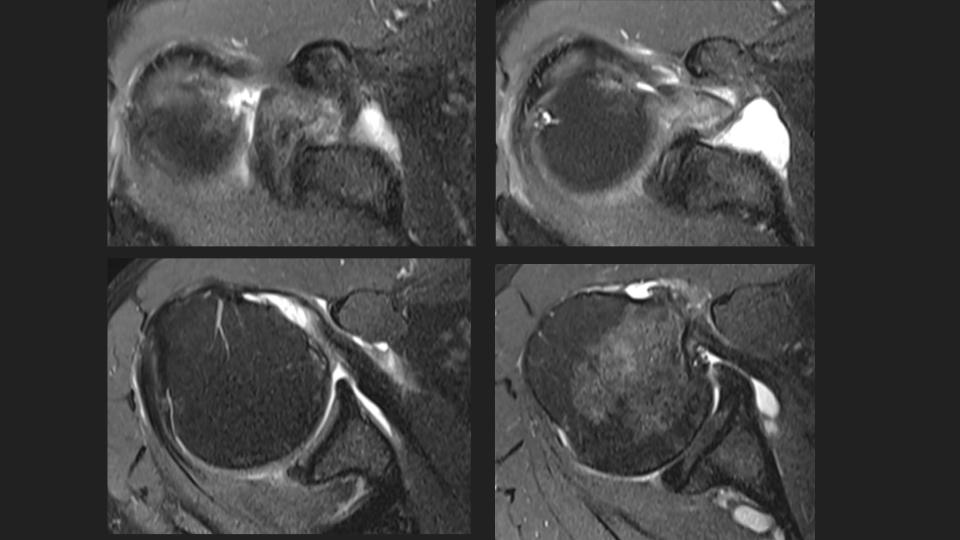

58M shoulder and upper arm pain x 4 weeks

There is a complete tear of the intraarticular long head biceps tendon (LHBT). The intraarticular remant is displaced into the superior subscapular recess and the torn retracted tendon is distal to the pec major insertion (bue arrow) in the mid upper arm (white arrow). Note the delaminating tear of the subscapularis tendon (red arrow). There is moderate supraspinatus tendinosis without tear (not shown).